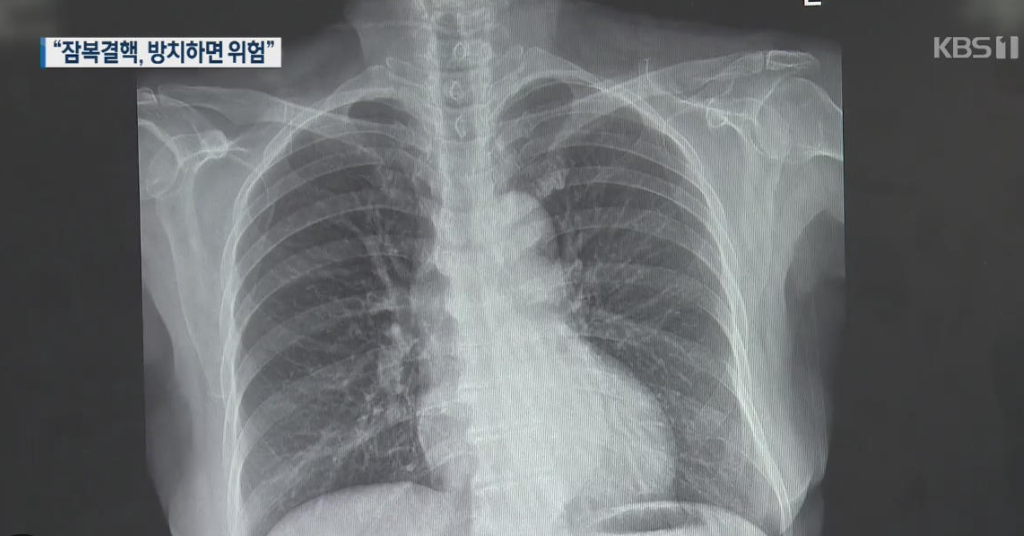

결핵 증상이 의심되거나, 최근 결핵 환자와 밀접 접촉한 적이 있다면 잠복결핵 검사도 고려해봐야 합니다. 국가에서는 밀접 접촉자, 의료기관 종사자, 노인복지시설 입소자 등 고위험군을 대상으로 무료 검사를 지원하고 있습니다.

결핵이 의심된다면 흉부 엑스레이, 객담검사, 필요시 CT 검사까지 받을 수 있으며, 대부분 국가에서 검사비를 지원합니다.